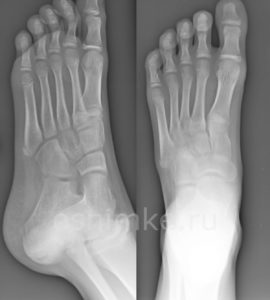

Исходя из наблюдаемой у пациента симптоматики, рентгенография стопы может проводиться в разных проекциях, с нагрузкой или без неё. Такой подход помогает провести подробную диагностику, спланировать терапевтический курс и проконтролировать результаты.

Выбор в пользу той или иной разновидности процедуры делается в зависимости от диагностируемой патологии (возрастные изменения костной ткани, врождённые недуги, артроз, механические повреждения костей и пр.).

Самый информативный диагностический метод — это рентген стопы в двух проекциях (прямой, боковой), когда снимок делают с обеспечением дополнительной нагрузки.

При съемке ступни в двух проекциях врачи получают два снимка: сбоку и сверху. Это позволяет более полно оценить состояние костей, суставов и мягких тканей стопы, выявить деформации и другие патологии.